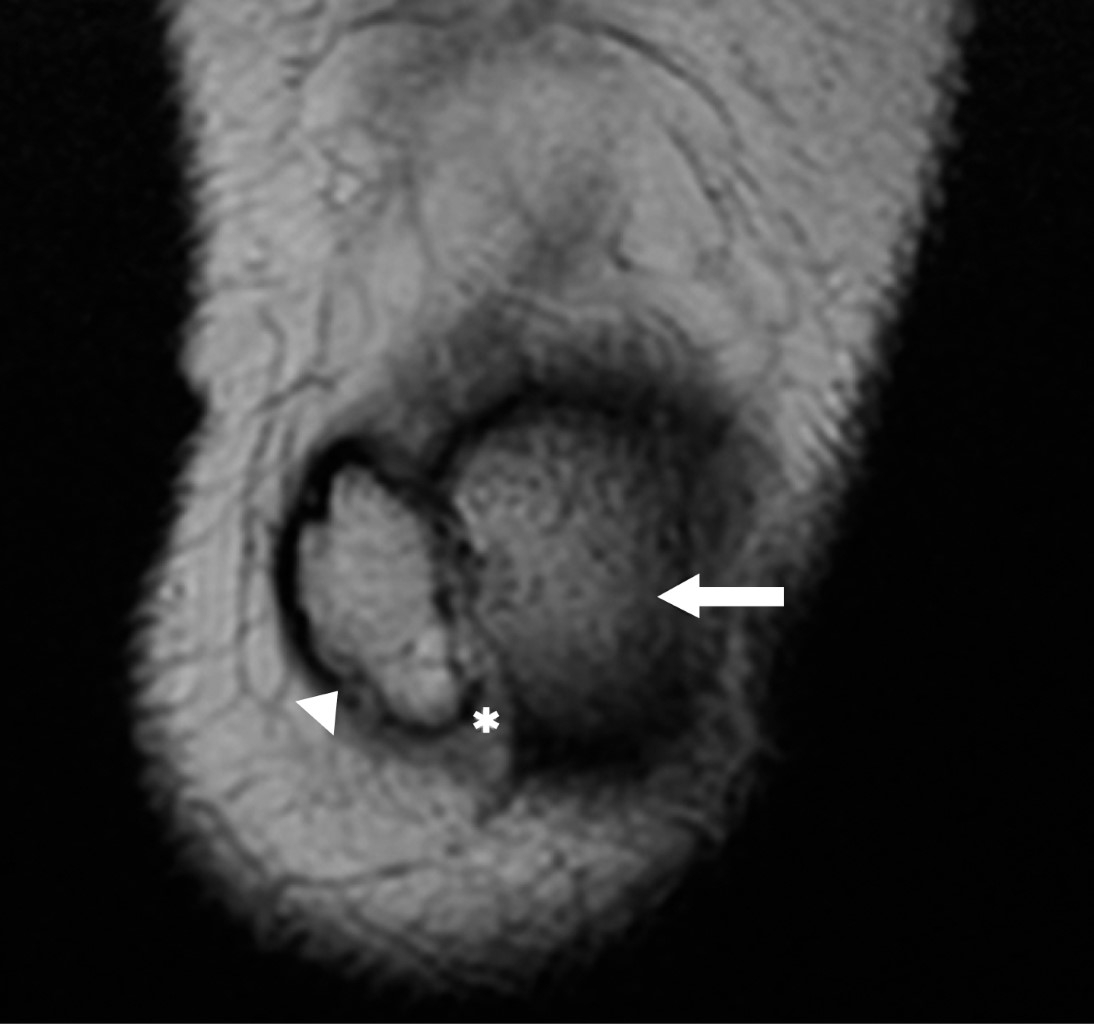

Patellar duplication is a rare entity, where a patella and an accessory patella develop from two ossification nuclei. This pathology can present with a variety of clinical problems depending on its stability. It is considered stable when there is soft tissue between the bone segments allowing little movement thereof. The most important pathology as a differential diagnosis is the bipartite patella, its main difference is that in the bipartite patella the fragments are joined by the continuous covering of the articular cartilage, and no extra ligamentous structures are observed.